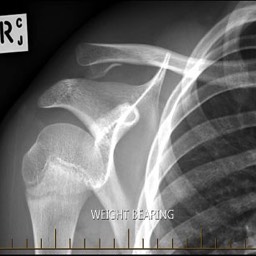

What do clavicle fractures look like on X-ray?

Below are examples of typical fractures that benefit from surgery.

Click an image to enlarge